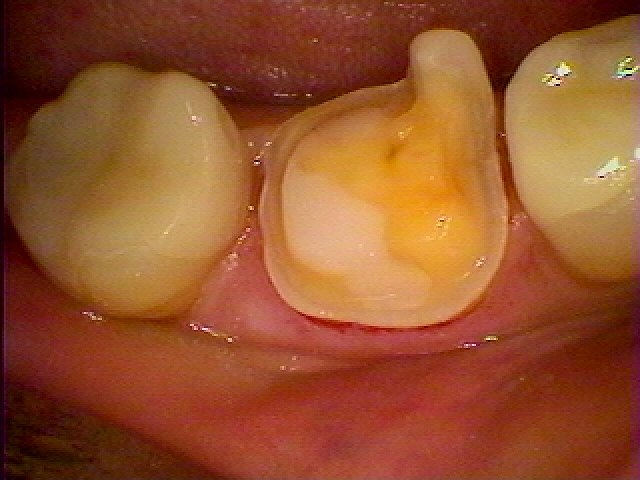

右下奥歯の大きな銀歯をやり変えたい 大きな銀歯が入っています|お知らせ |広島市安佐南区の歯科医院 右下奥歯の大きな銀歯をやり変えたい 大きな銀歯が入っています トップ お知らせ・ブログ お知らせ 右下奥歯の大きな銀歯をやり変えたい 大きな銀歯が入っています 右下奥歯の大きな銀歯をやり変えたい 大きな銀歯が入っています 大きな銀歯が入っていました 縁上マージン 銀歯をはずしていきました マージンが黒く虫歯になっていました 中は虫歯だらけになっていました 虫歯を取っていったところになりました セラミックにて修復を行いました 綺麗に仕上がりました Web診療予約 初めての方へ 選ばれ続ける理由 院内設備について 歯が痛いしみる一般歯科 歯がぐらぐらする歯周病 健康な歯を保ちたい予防歯科 子供の虫歯予防をしたい小児歯科 銀歯をセラミックに審美歯科 白い歯を目指しませんか?ホワイトニング 矯正専門医がいるので安心矯正歯科 抜けた歯を補いたいインプラント・入れ歯 医院案内 スタッフ紹介 メリィハウス歯科クリニックオフィシャルホームページ ラベンダー歯科クリニックオフィシャルホームページ お知らせ・ブログ ホーム 診療科目 一般歯科 歯周病治療 予防治療 小児歯科 審美治療 ホワイトニング 矯正歯科 入れ歯・インプラント マウスピース矯正 初めての方へ 院長・スタッフ 設備紹介 医院案内・アクセス メニューを閉じる